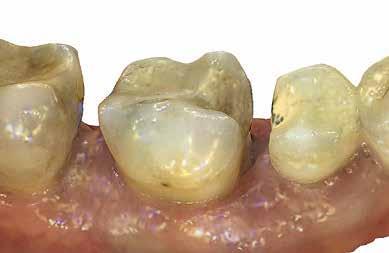

2. ábra: Az impaktált fog lézerrel asszisztált sebészi feltárása. 3. ábra: A kezelés megkezdését követő 15. hónapban megfigyelhető a sikeres felszabadítást, fogmozgatást és pozicionálást követően látható állapot.

6 hónapon keresztül tartott. Ennek megfelelően a fog körül található szövetek a felszabadítás, valamint a havi kontrollok során 975 nm-es (több mint 25 J/cm2 energiasűrűség) és 660 nm-es hullámhosszúságú (12–18 J/cm2 energiasűrűség) lézersugarakkal is megvilágításra kerültek. Az impaktálódott fogat megközelítőleg 7 hónap alatt tudtuk megfelelő pozícióba mozgatni (3. ábra). Az orthodoncia kezelés aktív szakasza 18 hónapon keresztül tartott. A fogívek végső nivellálását és a fogak végleges pozícióba rendezését 0.018 × 0.025-ös acélívekkel végeztük.

A kezelés befejezésekor a páciens mosolya drámai mértékben javult, továbbá a frontfogak elhelyezkedése és az ínyszél lefutása is szemmel látható módon kedvezőbbé vált (4. ábra). A kezelés végén készült CBCT felvétel nem mutatta

csontfelszívódás jelenlétét, és csupán minimális mértékű gyökérfelszívódás bekövetkezését igazolta.